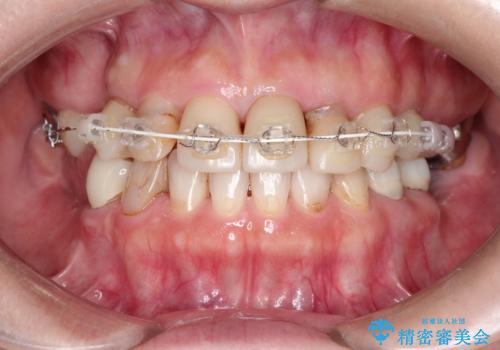

上顎の前歯はガタガタがあり、過去に治療した歯はつぎはぎのようになっており、審美的に周囲と調和がとれていない状態でした。

①仮歯を装着

②矯正治療

セラミックのかぶせ物だけで、歯並びまで変えようとするのには限界があります。